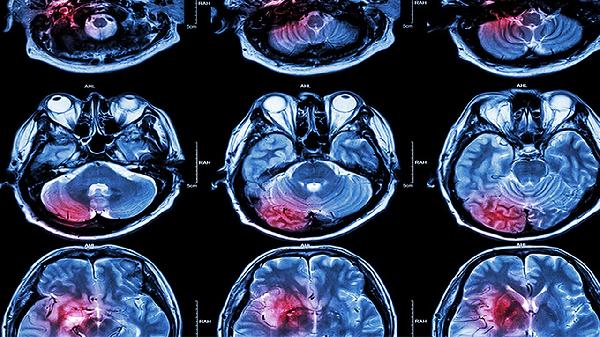

物理治疗能缓解肌肉痉挛和关节挛缩,常用功能性电刺激、经颅磁刺激等促进神经修复。水疗和热疗可改善局部血液循环,超声波治疗有助于软化瘢痕组织。对于吞咽障碍患者可采用冰刺激和电针治疗,需配合吞咽造影检查制定个体化方案。